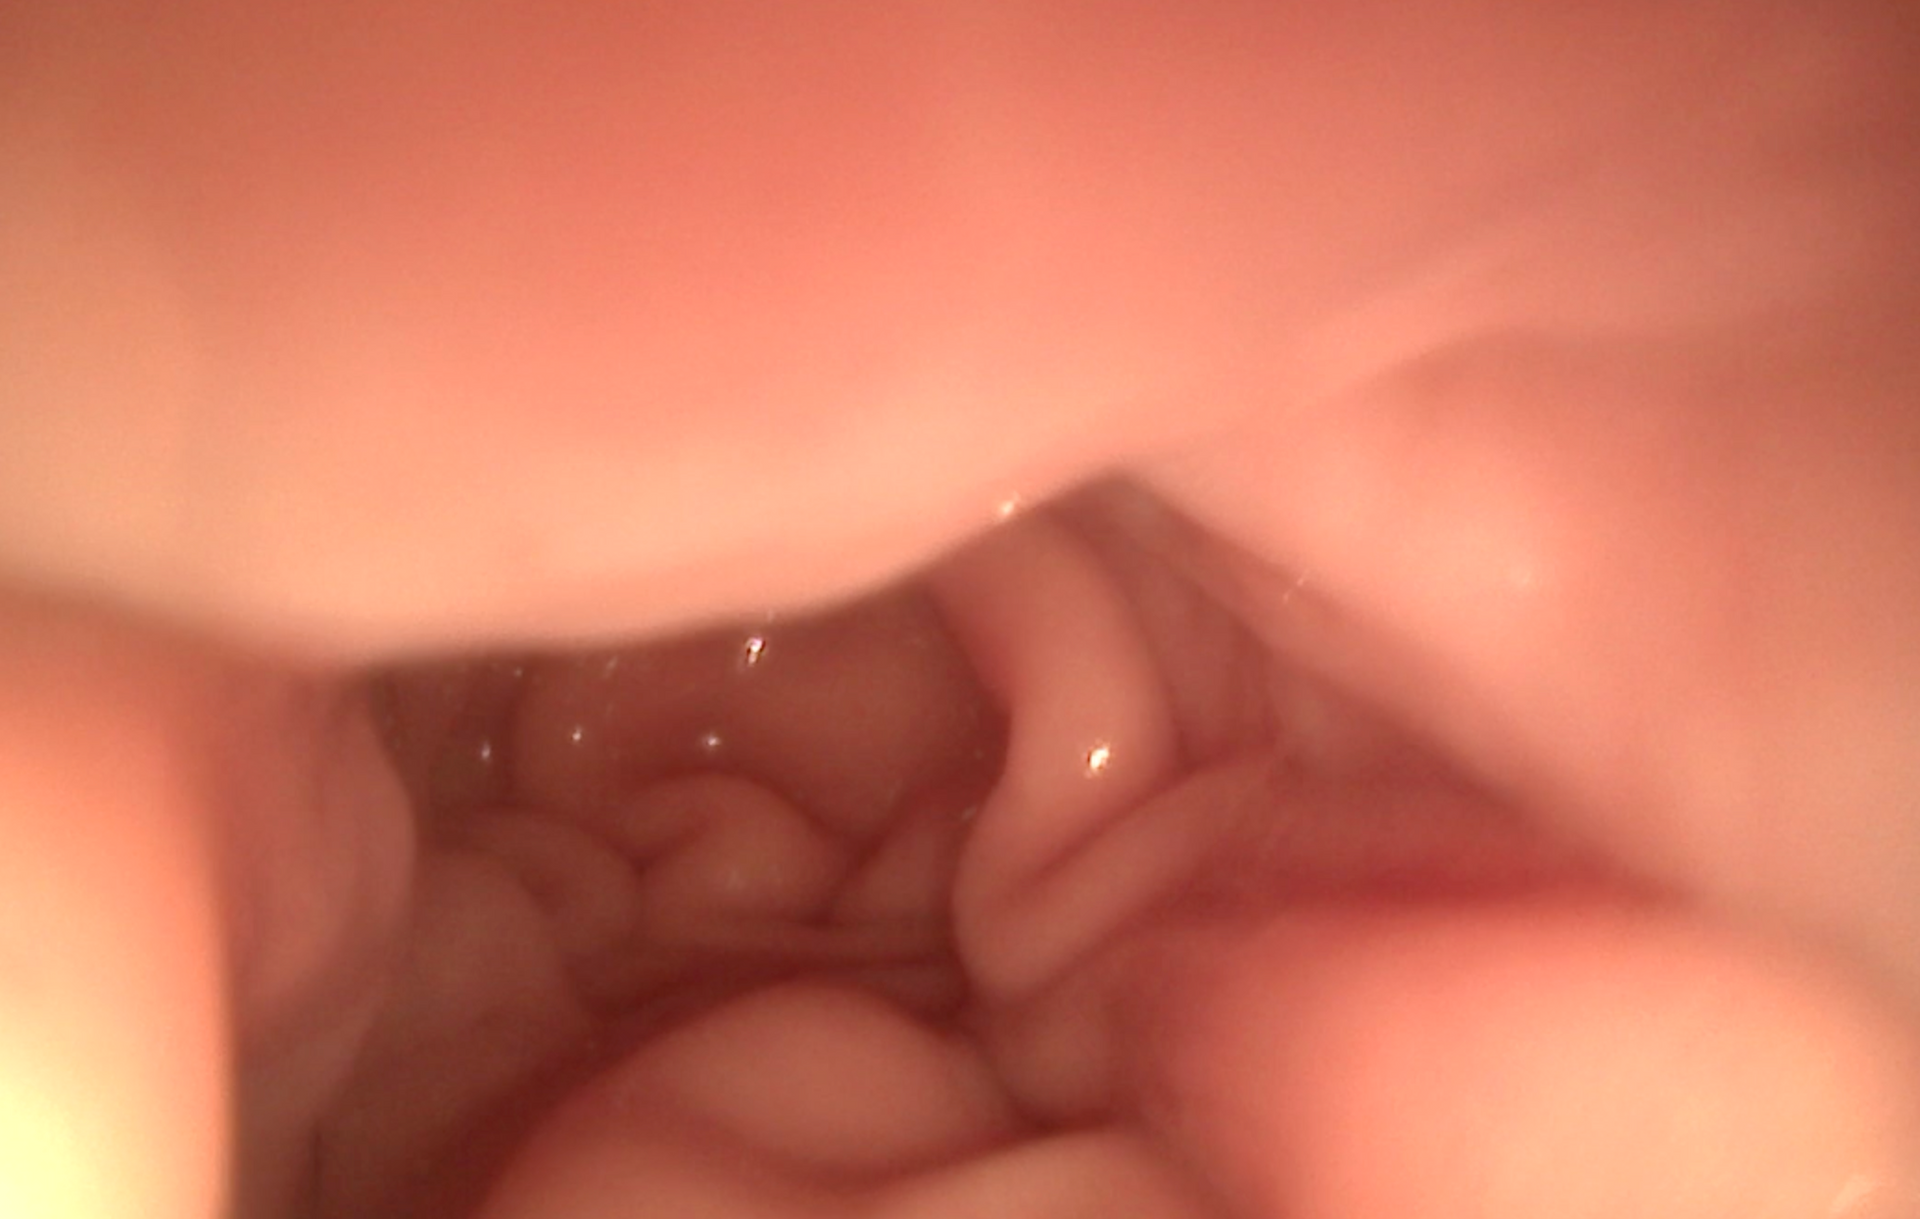

- Coloscopie → étude du côlon et du rectum (diarrhées chroniques, saignements)

- Cystoscopie → exploration de la vessie et de l’urètre (infections urinaires récidivantes, calculs, tumeurs)